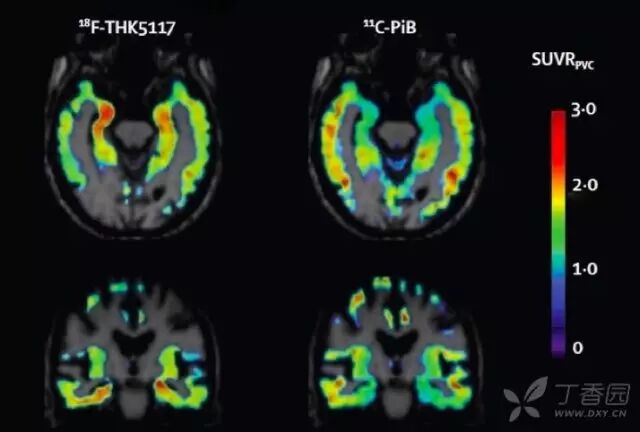

7. tau 蛋白成像

利用 tau 蛋白的氟化配体进行 tau 蛋白成像目前也是研究热点。tau 蛋白配体聚集与 AD 临床症状符合;且与 Amyloid PET 相比,与基础代谢率减退和脑萎缩更相关。目前 tau 成像主要用于临床药物试验,对于其临床诊断价值仍需进一步证实。

图 8  AD 患者以 18F-THK5117 和11C-PiB 为显影剂的 tau 蛋白和 Aβ成像 10